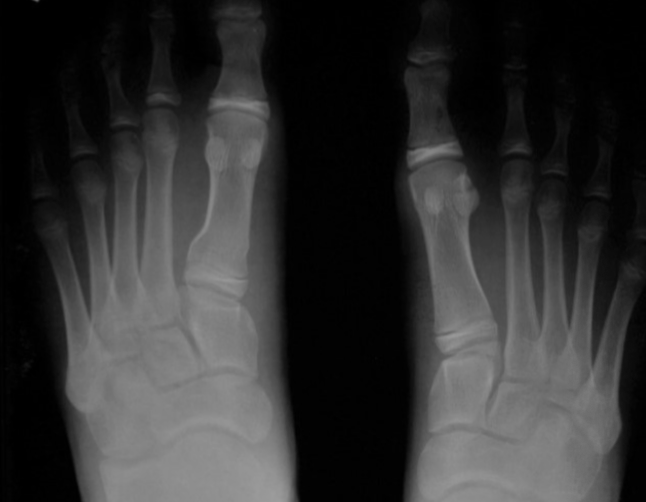

Comminuted fracture

multiple fracture lines exist in the same bone (3 or more fracture fragments)